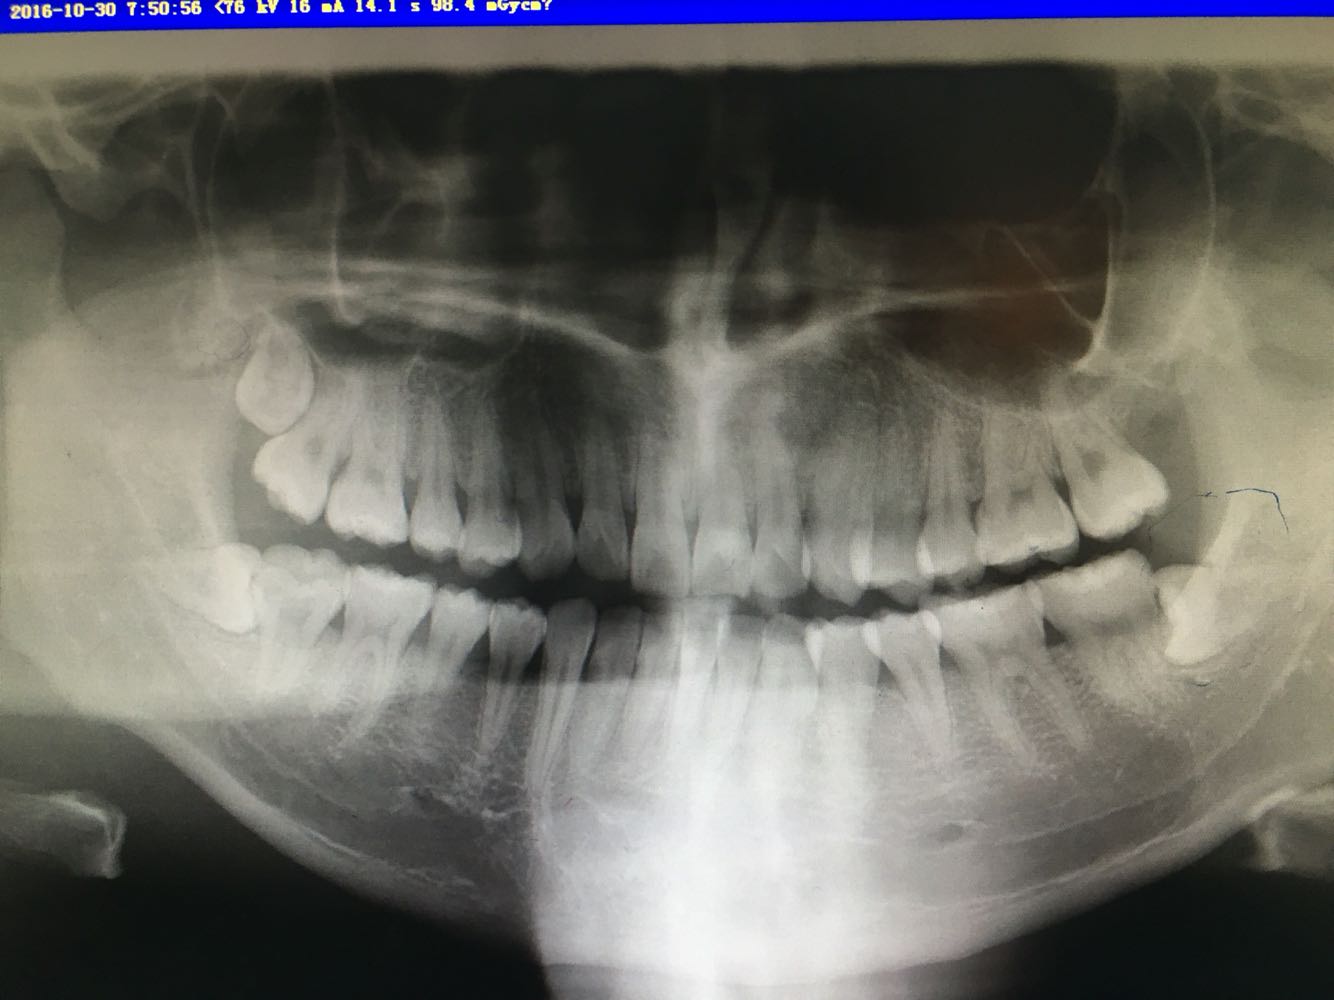

查体 辅查

查体:48牙齿水平阻生,牙龈无红肿,47无松动。 辅查:全景片,38,48牙齿水平阻生

诊断 处理

诊断:38,48阻生。 治疗:48牙齿局麻下拔除